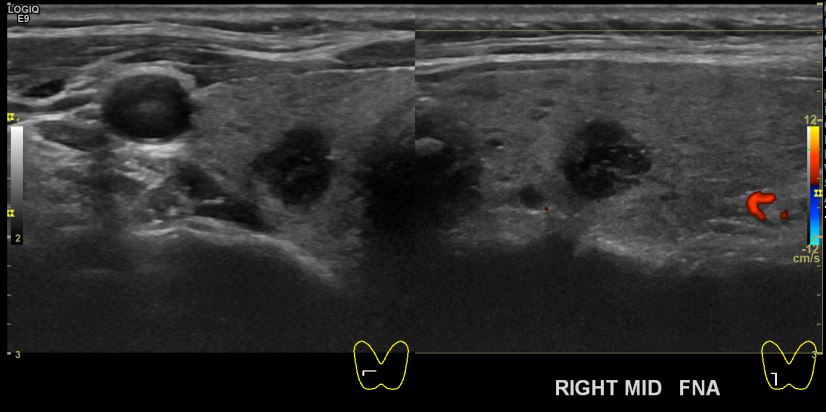

상기환자 외부검사이상소견으로 내원하신 50대후반 여성분으로 의심스러운 우엽혹 세포검사진행후 갑상선암으로 진단되었습니다